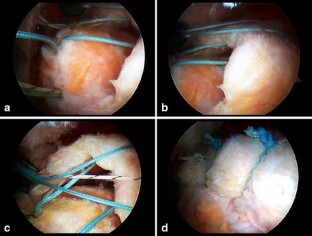

Fig. 3